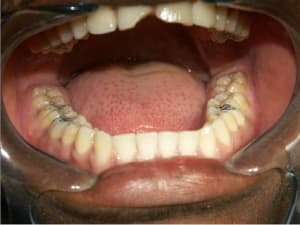

Cas_3_b_izilst.jpg

Voir le message contenant cette image